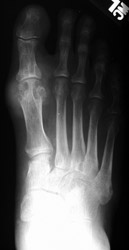

Gout: AP- Erosions 1st MTP joint with tophiGout: AP- Erosions 1st MTP joint with tophiTophaceus Gout: LateralTophaceus Gout: APGOUT is caused by monosodium urate or uric acid crystal deposition within cartilage, bone, or periarticular tissues.

First metatarsophalangeal joint is most commonly affected, followed by the first interphalangeal joint and tarsometatarsal joints. Posterior calcaneal involvement has also been noted. The majority of first presentations are monoarticular. Bilateral and symmetric or asymmetric polyarticular involvement may be present within any of the foot joints.

Acute, episodic soft tissue swelling may represent the earliest radiographic sign. Later, sharp, round or oval marginal joint erosions with sclerotic borders are classically seen with gout. These findings most commonly occur along the dorsum of the foot. Associated soft tissue tophi or intraosseous nodules may be present. "Overhanging margin" occur where the bone resorbs beneath a tophaceous nodule. Joint spaces are usually preserved, but ankylosis may rarely occur with advanced stages of gout. The aforementioned findings may be in different stages of progression with any given patient.